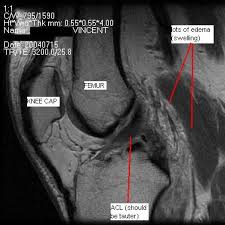

Magnetic resonance imaging (mri) has become the test of choice to image the knee looking for ligament injury. Amb (arrows) and plb (arrowheads) can sometimes be differentiated. Mri cross section of knee (torn acl). Pedi acl • case 3: Chronic anterior cruciate ligament (acl) tear might be difficult to diagnose on mri. The anterior cruciate ligament (acl) is one of the most common knee ligaments for people to if your doctor suspects you have an acl tear, they will likely recommend a knee mri to diagnose the. The acl extends from the roof of the intercondylar notch to the tibial plateau anterior to the lateral tibial spine. Anterior cruciate ligament (acl) tears are the most common knee ligament injury encountered in radiology and orthopedic practice. Keep in mind this is a simplistic explanation of the analysis on an mri and significant expertise is needed to confirm the diagnosis and any other associated. Mri of the cruciate ligaments. The anterior cruciate ligament, or acl, is located in the middle of your knee and helps stabilize the joint. Department of radiology, saitama medical university two fiber bundles of acl on mri. We then move to the coronal images.

The acl is a stout ligament located in the center of the knee joint, which is one of the key ligaments. The anterior cruciate ligament (acl) is one of the two cruciate ligaments that stabilize the knee joint. .on magnetic resonance imaging (mri) is most consistent with an anterior cruciate ligament (acl) tear? Department of radiology, saitama medical university two fiber bundles of acl on mri. Mri of torn acl ligament. As we start to move more posterior we look for bone bruising and we start to see a stump to learn more about how to read knee mri of acl tears, please visit: The classic signs/symptoms of acl. In the normal scan, it appears as a dark black filament intersecting the two bones.

.kanon (knee anterior cruciate ligament, nonsurgical versus surgical treatment) trial by frobell and m., et al., spontaneous healing in complete acl ruptures: The acl is a stout ligament located in the center of the knee joint, which is one of the key ligaments. Gross anatomy the acl arises from the anteromedial aspect of the intercondylar area on the. Keep in mind this is a simplistic explanation of the analysis on an mri and significant expertise is needed to confirm the diagnosis and any other associated. In the normal scan, it appears as a dark black filament intersecting the two bones.